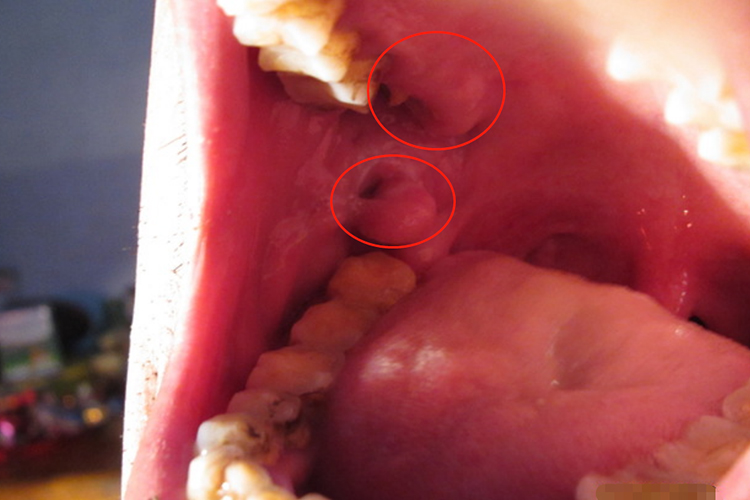

浆细胞龈炎:本病主要发生于牙龈,可侵犯多个牙齿或上下颌同时受累。牙龈鲜红、肿大、松软易破,表面似半透明状,有时如肉芽组织状,表面呈结节状或分叶状。极易出血,常并发不同程度的感染,有溢脓、口臭。

药物性牙龈增生:可呈球状、结节状或桑葚状突起于牙龈表面,向边缘扩展,覆盖部分牙面,像长了一个小肉芽一样。严重者妨碍进食。牙龈呈淡粉红色,质地坚硬,略有弹性,一般不易出血。无自觉症状,无疼痛。

牙龈瘤:通常呈圆形、椭圆形,有时呈分叶状。大小不一,从数毫米至1-2厘米,看着像长了一个小肉芽,质地较软、色红,一般无痛,肿物表面发生溃疡时可自觉疼痛。